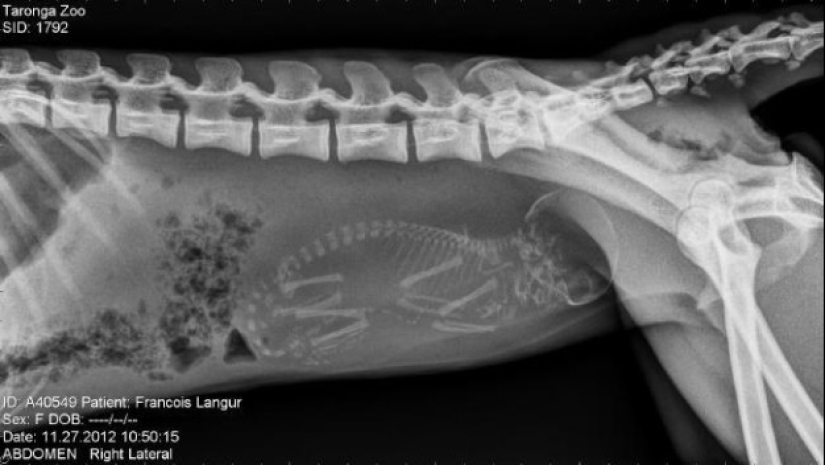

mono preñado